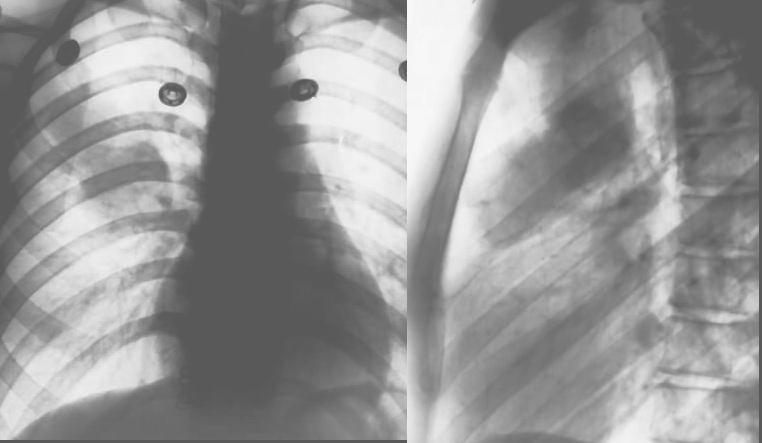

标题: X4932:女,22岁.体检发现.请各位分析可能是什么. [打印本页]

标题: X4932:女,22岁.体检发现.请各位分析可能是什么.

右肺上叶前段病变,临床资料太少,不好定。建议查血象、ct进一步检查。

右肺上叶前段病变,因是体检发现,估计没有临床症状,考虑良性占位,不除外结核。

考虑右肺上叶良性肿块;建议行进一步检查。

病灶位于上叶前段,不是结核好发部位,不过患者较年轻,又是体检才发现的,考虑结核可能性大,但单就一平片,很难做出最后更有说服力的结论,所以还是建议ct